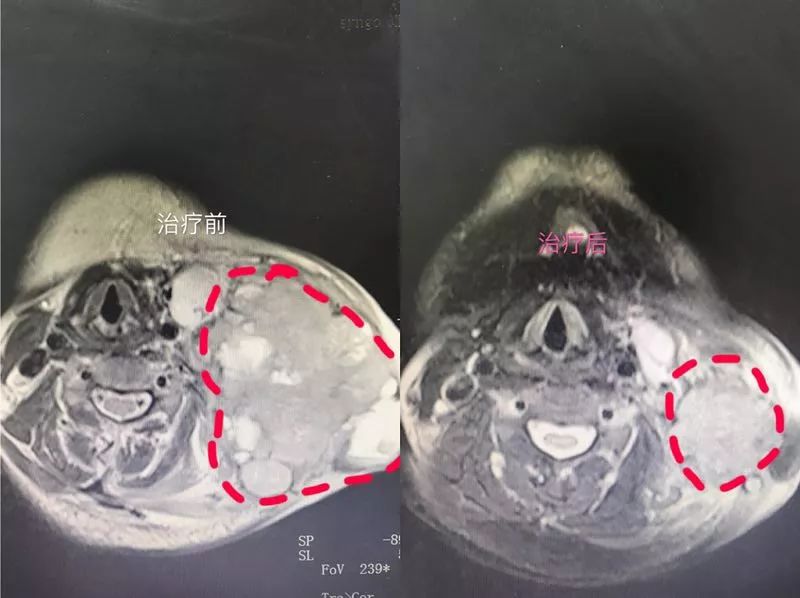

今年3月,胡大姐来到复大肿瘤医院,一开始应用TPF方案治疗鼻咽癌无明显效果,主治医生陈月荣为她采用尼妥珠单抗与紫杉醇(白蛋白结合型)化疗方案,从药物分析上看,这也是非常有效的鼻咽癌化疗药,果然,胡大姐的肿瘤逐渐缩小,仅两个周期靶向药物治疗11.5×10.7厘米巨大鼻咽癌转移瘤就缩小成5.8×4.2厘米。

治疗前后对比